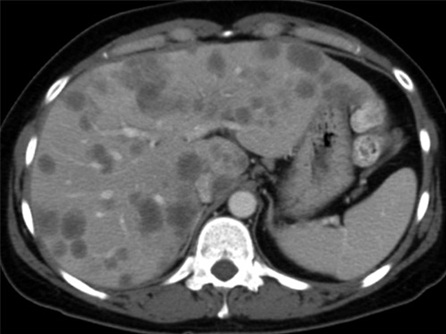

O câncer colorretal frequentemente se espalha para o fígado, e a metástase hepática é uma complicação comum e séria. A intervenção cirúrgica desempenha um papel crucial no manejo dessas metástases. O tratamento cirúrgico pode oferecer uma chance significativa de cura ou prolongamento da sobrevivência para pacientes com metástases hepáticas ressecáveis.

Tratamento Cirúrgico das Metástases Hepáticas

Ressecção Hepática Metastática: A remoção cirúrgica das áreas do fígado afetadas por metástases colorretais. Pode ser realizada em pacientes com um número limitado de metástases e função hepática adequada.

Terapias Combinadas: A cirurgia é frequentemente combinada com quimioterapia neoadjuvante (antes da cirurgia) para reduzir o tamanho das metástases, ou adjuvante (após a cirurgia) para eliminar células cancerígenas remanescentes.

Abordagens Minimamente Invasivas: Procedimentos como a ablação por radiofrequência podem ser usados para tratar pequenas metástases, especialmente em pacientes que não são candidatos à cirurgia aberta.

A Importância do Tratamento Cirúrgico

A cirurgia oferece a melhor chance de cura para pacientes com câncer de fígado em estágio inicial e para aqueles com metástases hepáticas de câncer colorretal ressecáveis. A remoção completa do tumor ou das metástases pode levar à remissão da doença e melhorar significativamente a qualidade de vida do paciente. Mesmo em casos avançados, a cirurgia pode ajudar a controlar os sintomas e prolongar a sobrevivência.

O câncer de fígado e as metástases hepáticas do câncer colorretal são condições graves que requerem diagnóstico precoce e tratamento adequado. A cirurgia é uma abordagem fundamental no tratamento dessas doenças, oferecendo a melhor chance de cura e controle da doença. Pacientes devem estar atentos aos sinais e sintomas e procurar atendimento médico imediatamente se houver suspeita de problemas hepáticos. Consultas regulares e exames de rotina são essenciais para a detecção precoce e o tratamento eficaz. Se você tiver qualquer sintoma ou preocupação, não hesite em buscar orientação médica.